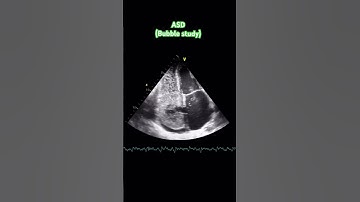

Why Is An Echocardiogram Important For Finding ASD In Stroke Patients? - Stroke Support Channel